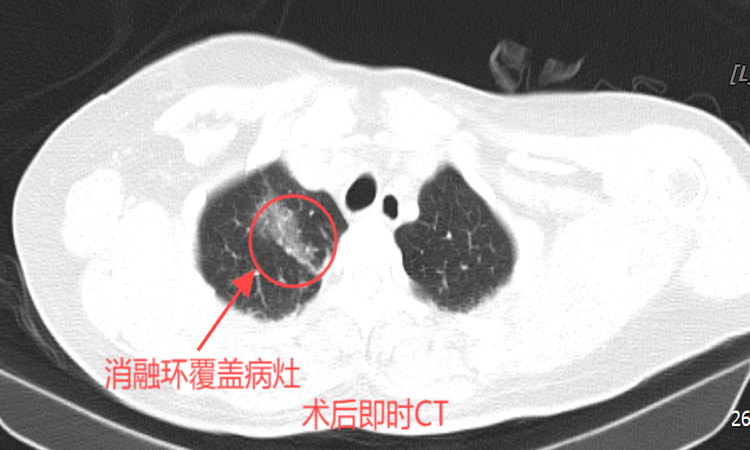

在征得患者及家属同意后,刘冰主任带领团队进行了肺部多发结节微波消融术。术中,选取患者合适体位,CT确认进针通道,然后在CT引导下精准置入微波消融针至结节处进行消融。40分钟后,手术顺利完成,复查胸部CT显示:消融治疗范围覆盖目标病灶,无气胸及出血。术后患者没有特殊不适,安全返回病房。